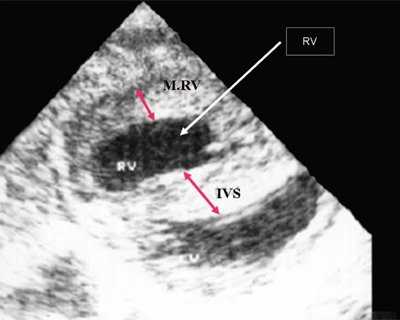

Нагрузка сопротивлением возникает при ситуации, когда выброс крови из желудочков сердца в магистральные сосуды затруднен на уровне полулунных клапанов (стеноз аорты и легочной артерии), подклапанного пространства (идиопатический гипертрофический субаортальный стеноз, подклапанный стеноз аорты или легочной артерии), на протяжении сосудистого русла (коарктация аорты) либо при значительном увеличении выходного сопротивления (синдром Эйзенменгера). В результате затруднения выброса крови резко возрастает напряжение миокарда соответствующего желудочка при относительно стабильном объеме крови, что служит проявлением систолической перегрузки сердца. При систолической перегрузке желудочков сердца независимо от нозологической формы порока полость желудочка, несущего основную нагрузку сопротивлением, умеренно увеличивается в размерах. В ответ на нагрузку сопротивлением на эхокардиограмме выявляется гипертрофия миокарда соответствующего желудочка, и чем больше сопротивление выбросу, тем резче выражена степень гипертрофии миокарда соответствующего желудочка и межжелудочковой перегородки (рис. 1) [3].

Рис. 1. Систолическая перегрузка правого желудочка. Поперечное сечение желудочков сердца при стенозе легочной артерии. Градиент давления правый желудочек - легочная артерия равен 200 мм рт.ст. Выраженная гипертрофия межжелудочковой перегородки и миокарда передней стенки правого желудочка.